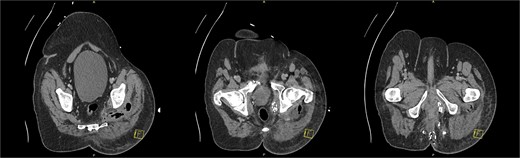

CT pelvis (axial slices) demonstrating the perianal surgical site with packing, and the gas and fluid containing intergluteal collection.